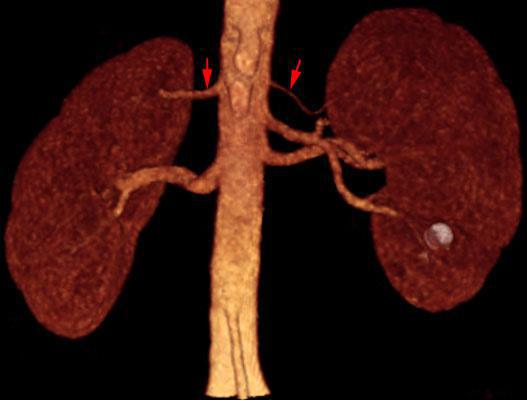

Arterias renales múltiples